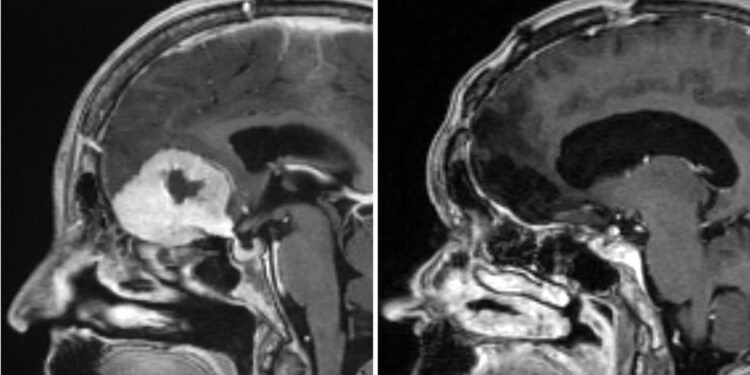

A surgeon is removing brain tumours “the size of large apples” through patients’ eyebrows, in what is believed to be a world first.

Dealing with tumours at the front of the brain normally requires surgeons to remove a large portion of the skull – exposing healthy parts of the brain in the process – in what is known as a craniotomy.

Mr Giamouriadis who works for NHS Grampian said this type of surgery is not new, but he has modified it to give him “more space, through the eyebrow” allowing him “to remove very big brain tumours”.

The technique is “a game-changer and much less invasive”, he said. “Traditionally people would be left with scars across their full forehead, we avoid that with this method.”

“Before we needed do a craniotomy to give us full access. That takes a very long time. To get to the tumour takes up to three hours alone. In total that approach will take eight to 10 hours.”

Doreen Adams, 75, underwent a craniotomy to remove a tumour abroad before later undergoing the eyebrow method last year – known as the Modified Eyebrow Keyhole SupraOrbital Approach for Brain Tumours.